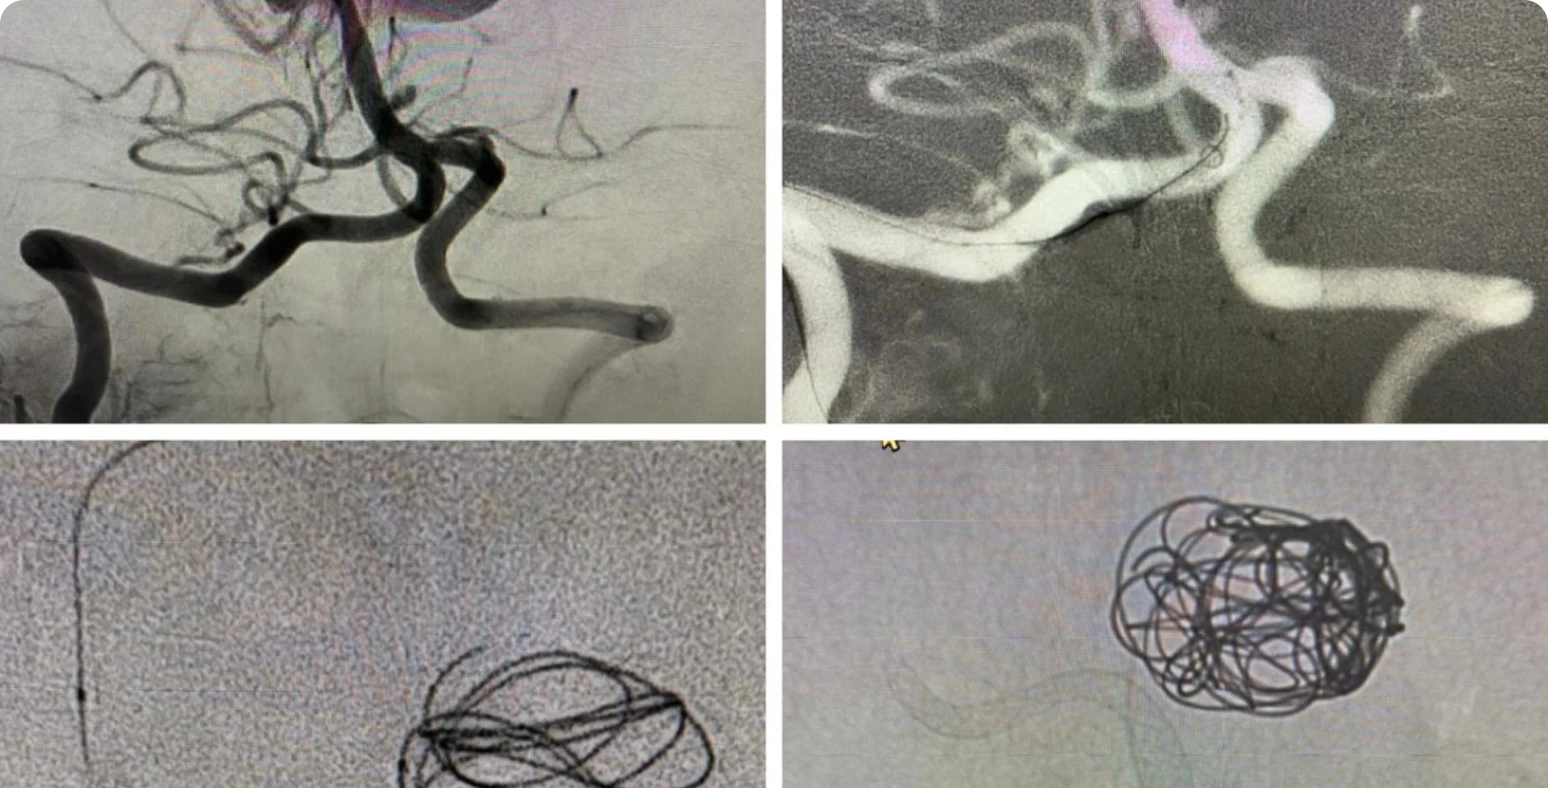

I’d like to share this case of, Cerebral dural AV fistula embolization using histocryl (n-Butyl cyanoacrylate) at Vellammal hospital and medical […]